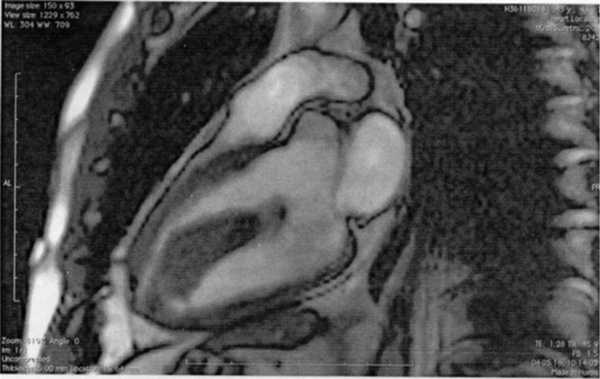

Магнитно-резонансная томография (МРТ) (рис. 2) зарегистрировала объемное образование (тромб) ЛЖ, исходившее из его верхушки, размером 1,8×6,6 см. Оно не было фиксировано к сосочковым мышцам, соприкасалось с передней створкой МК, не накапливало контрастного вещества. Обращали внимание интраоперационные фиброзные изменения, гипокинез МЖП и передней стенки ЛЖ.

Рис. 2. МРТ больного А., 43 лет. Диагноз: объемное образование (тромб) левого желудочка.